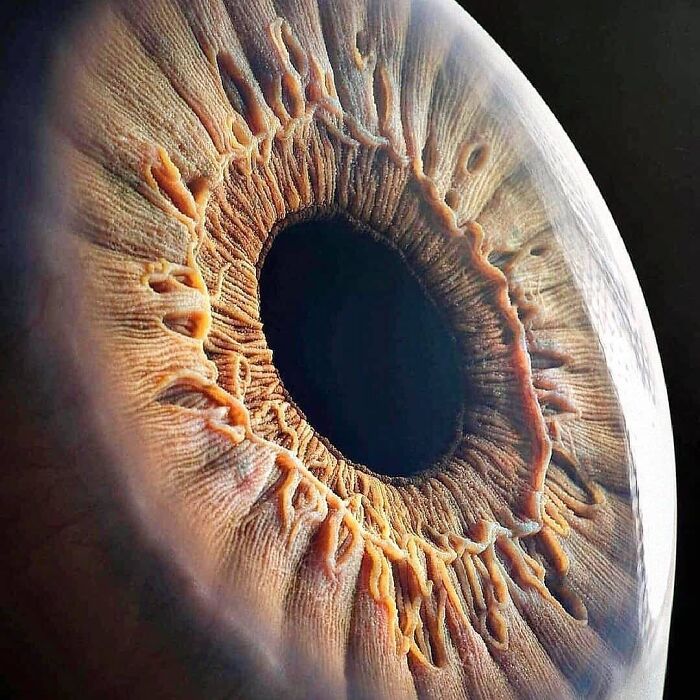

#7 Krásny detailný záber ľudského oka